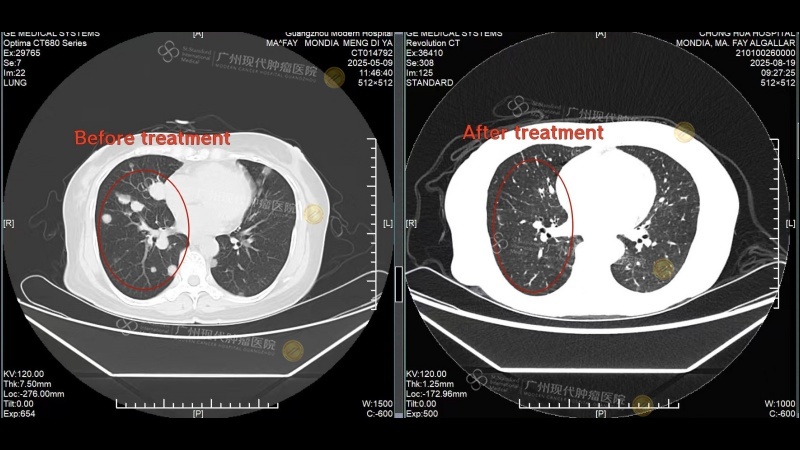

Comparison of lung metastases before and after treatment

After completing the 2nd treatment session, a follow-up CT scan at her local hospital revealed significant shrinkage of the breast tumor and the disappearance of most lung metastases. These remarkable results rekindled her hope—what she once believed was an insurmountable battle now seemed winnable at Modern Cancer Hospital Guangzhou.